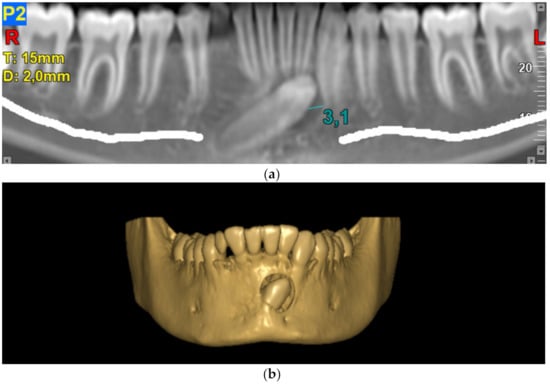

3. Results